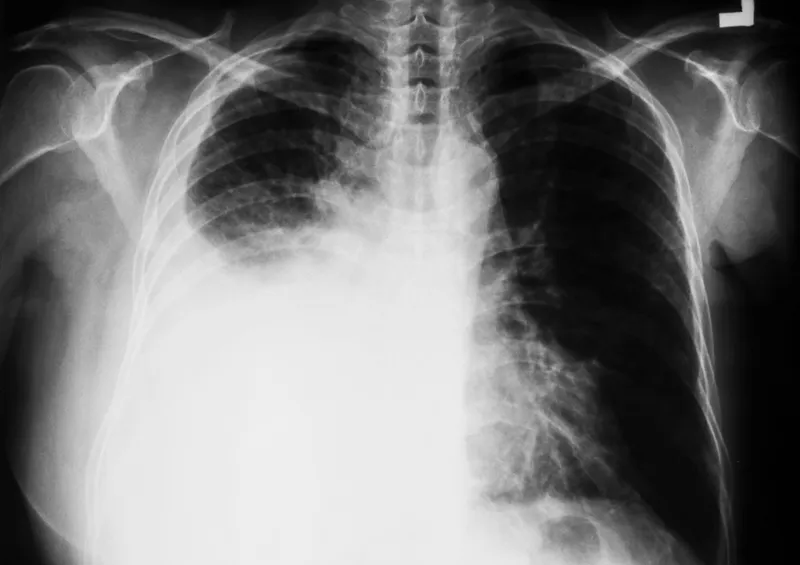

- CXR: Costophrenic angle blunting (~200 mL), meniscus. Lateral decubitus (~50 mL).

Malignant Pleural Effusion: Primary (mesothelioma) or metastases (lung, breast, lymphoma).

- Large, recurrent, often hemorrhagic. Dx: Cytology/pleural biopsy.

- Mesothelioma: Pleural malignancy.

- 📌 Risk: Asbestos exposure (primary).

- Imaging: Unilateral effusion, rind-like pleural thickening.

⭐ Strongly linked to occupational asbestos exposure; long latency (20-40 yrs).